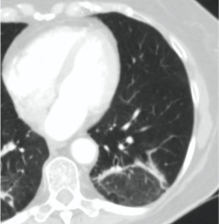

КТ имеет высокую чувствительность в выявлении изменений в легких, характерных для COVID-19. Применение КТ целесообразно для первичной оценки состояния ОГК у пациентов с тяжелыми прогрессирующими формами заболевания, а также для дифференциальной диагностики выявленных изменений и оценки динамики процесса. КТ позволяет выявить характерные изменения в легких у пациентов с COVID-19 еще до появления положительных лабораторных тестов на инфекцию с помощью МАНК. В то же время, КТ выявляет изменения легких у значительного числа пациентов с бессимптомной и легкой формами заболевания, которым не требуется госпитализация. Результаты КТ в этих случаях не влияют на тактику лечения и прогноз заболевания при наличии лабораторного подтверждения COVID-19. Поэтому массовое применение КТ для скрининга асимптомных и легких форм болезни не рекомендуется.

3. Применение лучевых методов у пациентов с симптомами ОРВИ легкой степени тяжести и стабильном состоянии пациента, возможно только по конкретным клиническим показаниям, в том числе при наличии факторов риска, при условии достаточных технических и организационных возможностей. Методом выбора в этом случае является КТ легких по стандартному протоколу без внутривенного контрастирования или РГ при ограниченной доступности КТ. Использование УЗИ в этих случаях нецелесообразно. Применение КТ исследования в сроки ранее 3 - 5 дней с момента появления симптомов заболевания является нецелесообразным.

5. Рекомендовано проведение лучевого исследования пациентам при среднетяжелом, тяжелом и крайне тяжелом течении ОРИ с целью медицинской сортировки, оценки характера изменений в грудной полости и определения прогноза заболевания:

- выполнение КТ легких без внутривенного контрастирования в стационарных условиях или в амбулаторных - при показаниях к госпитализации;